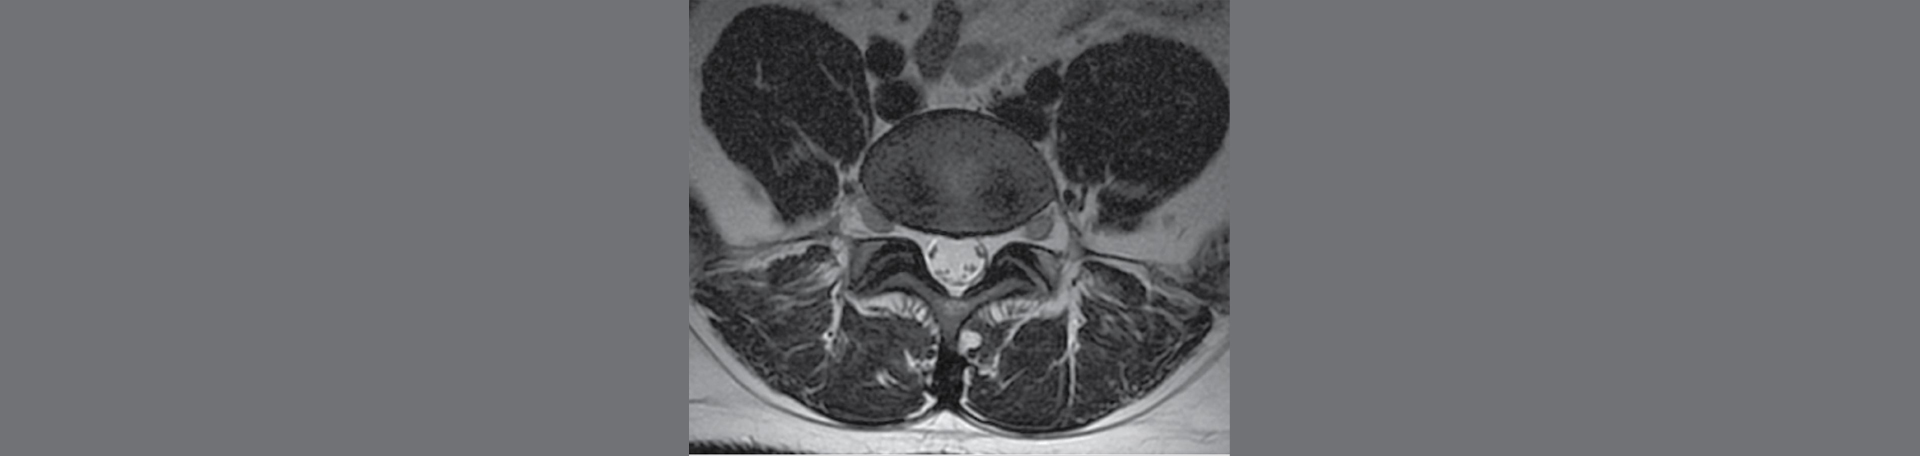

MEASURING DISC CHANGES WITH MAGNETIC RESONANCE SPECTROSCOPY

Magnetic resonance spectroscopy is a revolutionary imaging technique that goes beyond traditional MRI by quantifying the chemical composition of tissues. It gives insights into the biochemical make up of the spinal disc, allowing healthcare professionals to measure changes at a molecular level. This capability is vital to understanding how spinal manipulation can stimulate positive alterations in the disc's structure and function.

A momentous study by Billham et al. (2024) demonstrated significant alterations in intervertebral disc composition after the application of Cox® Flexion Distraction. The researchers detected alterations in the levels of essential metabolites, such as proteoglycans and collagen, which play critical roles in disc integrity and resilience. These findings highlight the potential of spinal manipulation to facilitate disc regeneration and improve overall spinal health. (1)

Supporting this concept, Li et al. (2024) created and just reported on an innovative way to use MRI histogram analysis to evaluate lumbar disc degeneration. Their study provided quantitative data that further validated the positive effects of spinal manipulative therapy on disc composition and structure. (2) Further, Majumdar's (2006) earlier work on MRI and spectroscopy of the intervertebral disc highlighted the ability of MRS to demonstrated valuable insights into the disc's condition. (3) These findings emphasize the significance of including advanced imaging techniques in assessing the efficacy of SMT and other therapeutic interventions like those we use every day here at Aurora Chiropractic Center. We look to provide evidence based spine care!